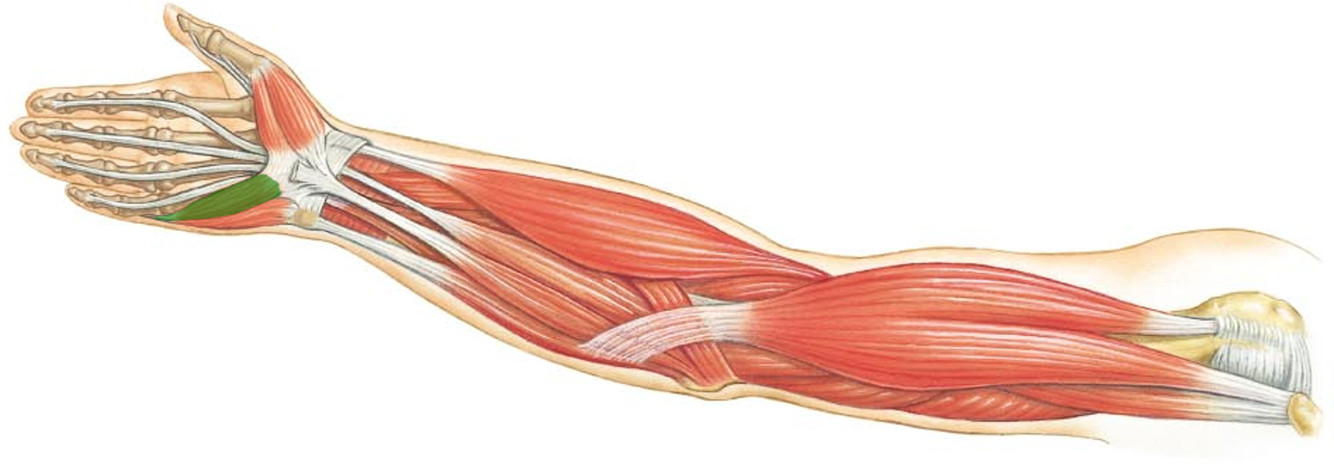

What is the innervation of this muscle?

Muscle - Flexor pollicus brevis

Median nerve

What is the innervation of this muscle?

Muscle - Opponens pollicus

Median Nerve